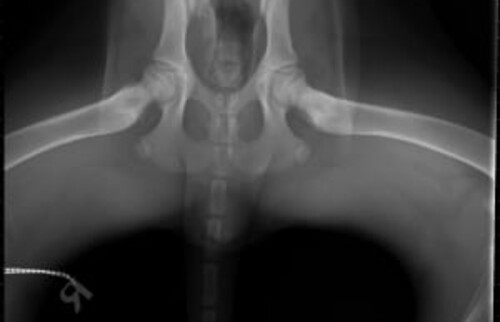

Bilder einer vollständigen Hüftdysplasie-Untersuchung beim Hund

In unserer Tierklinik bei Karlsruhe können unsere Ärzt*innen durch die Aufnahmen eine zuverlässige Prognose für die Weiterentwicklung der Hunde-Hüfte stellen.

Schwarz-weißes Röntgenbild der Hüftgelenke eines Tieres mit weit nach außen gespreizten Hinterbeinen.